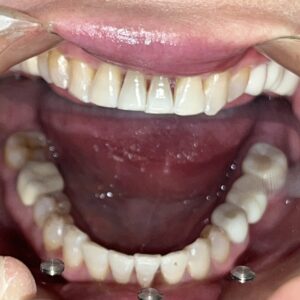

こちらが実際のセット後の写真です。

上の犬歯から犬歯までの6本の歯に審美治療を行っています。

治療のタイミングが異なるため

メタルセラミック、レイヤリングジルコニア、

ジルコニアラミネートべニア(付け爪のように薄いジルコニアを張り付ける方法)

等の材料をつかっています。

スーパーセラミスト常泉氏(ホームページ参照)が丹念に製作しております。

自然で美しい仕上がりに満足いただけています。